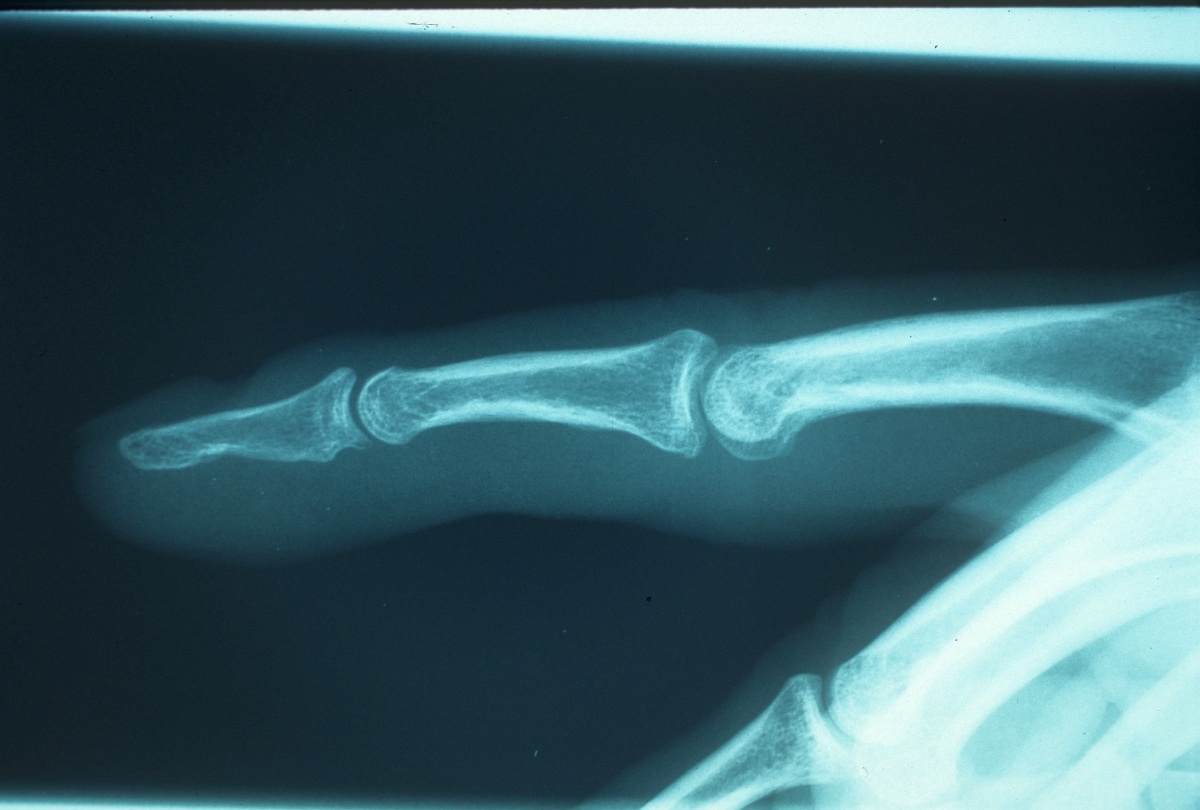

Radiographs confirm debridement.

Three months postop.